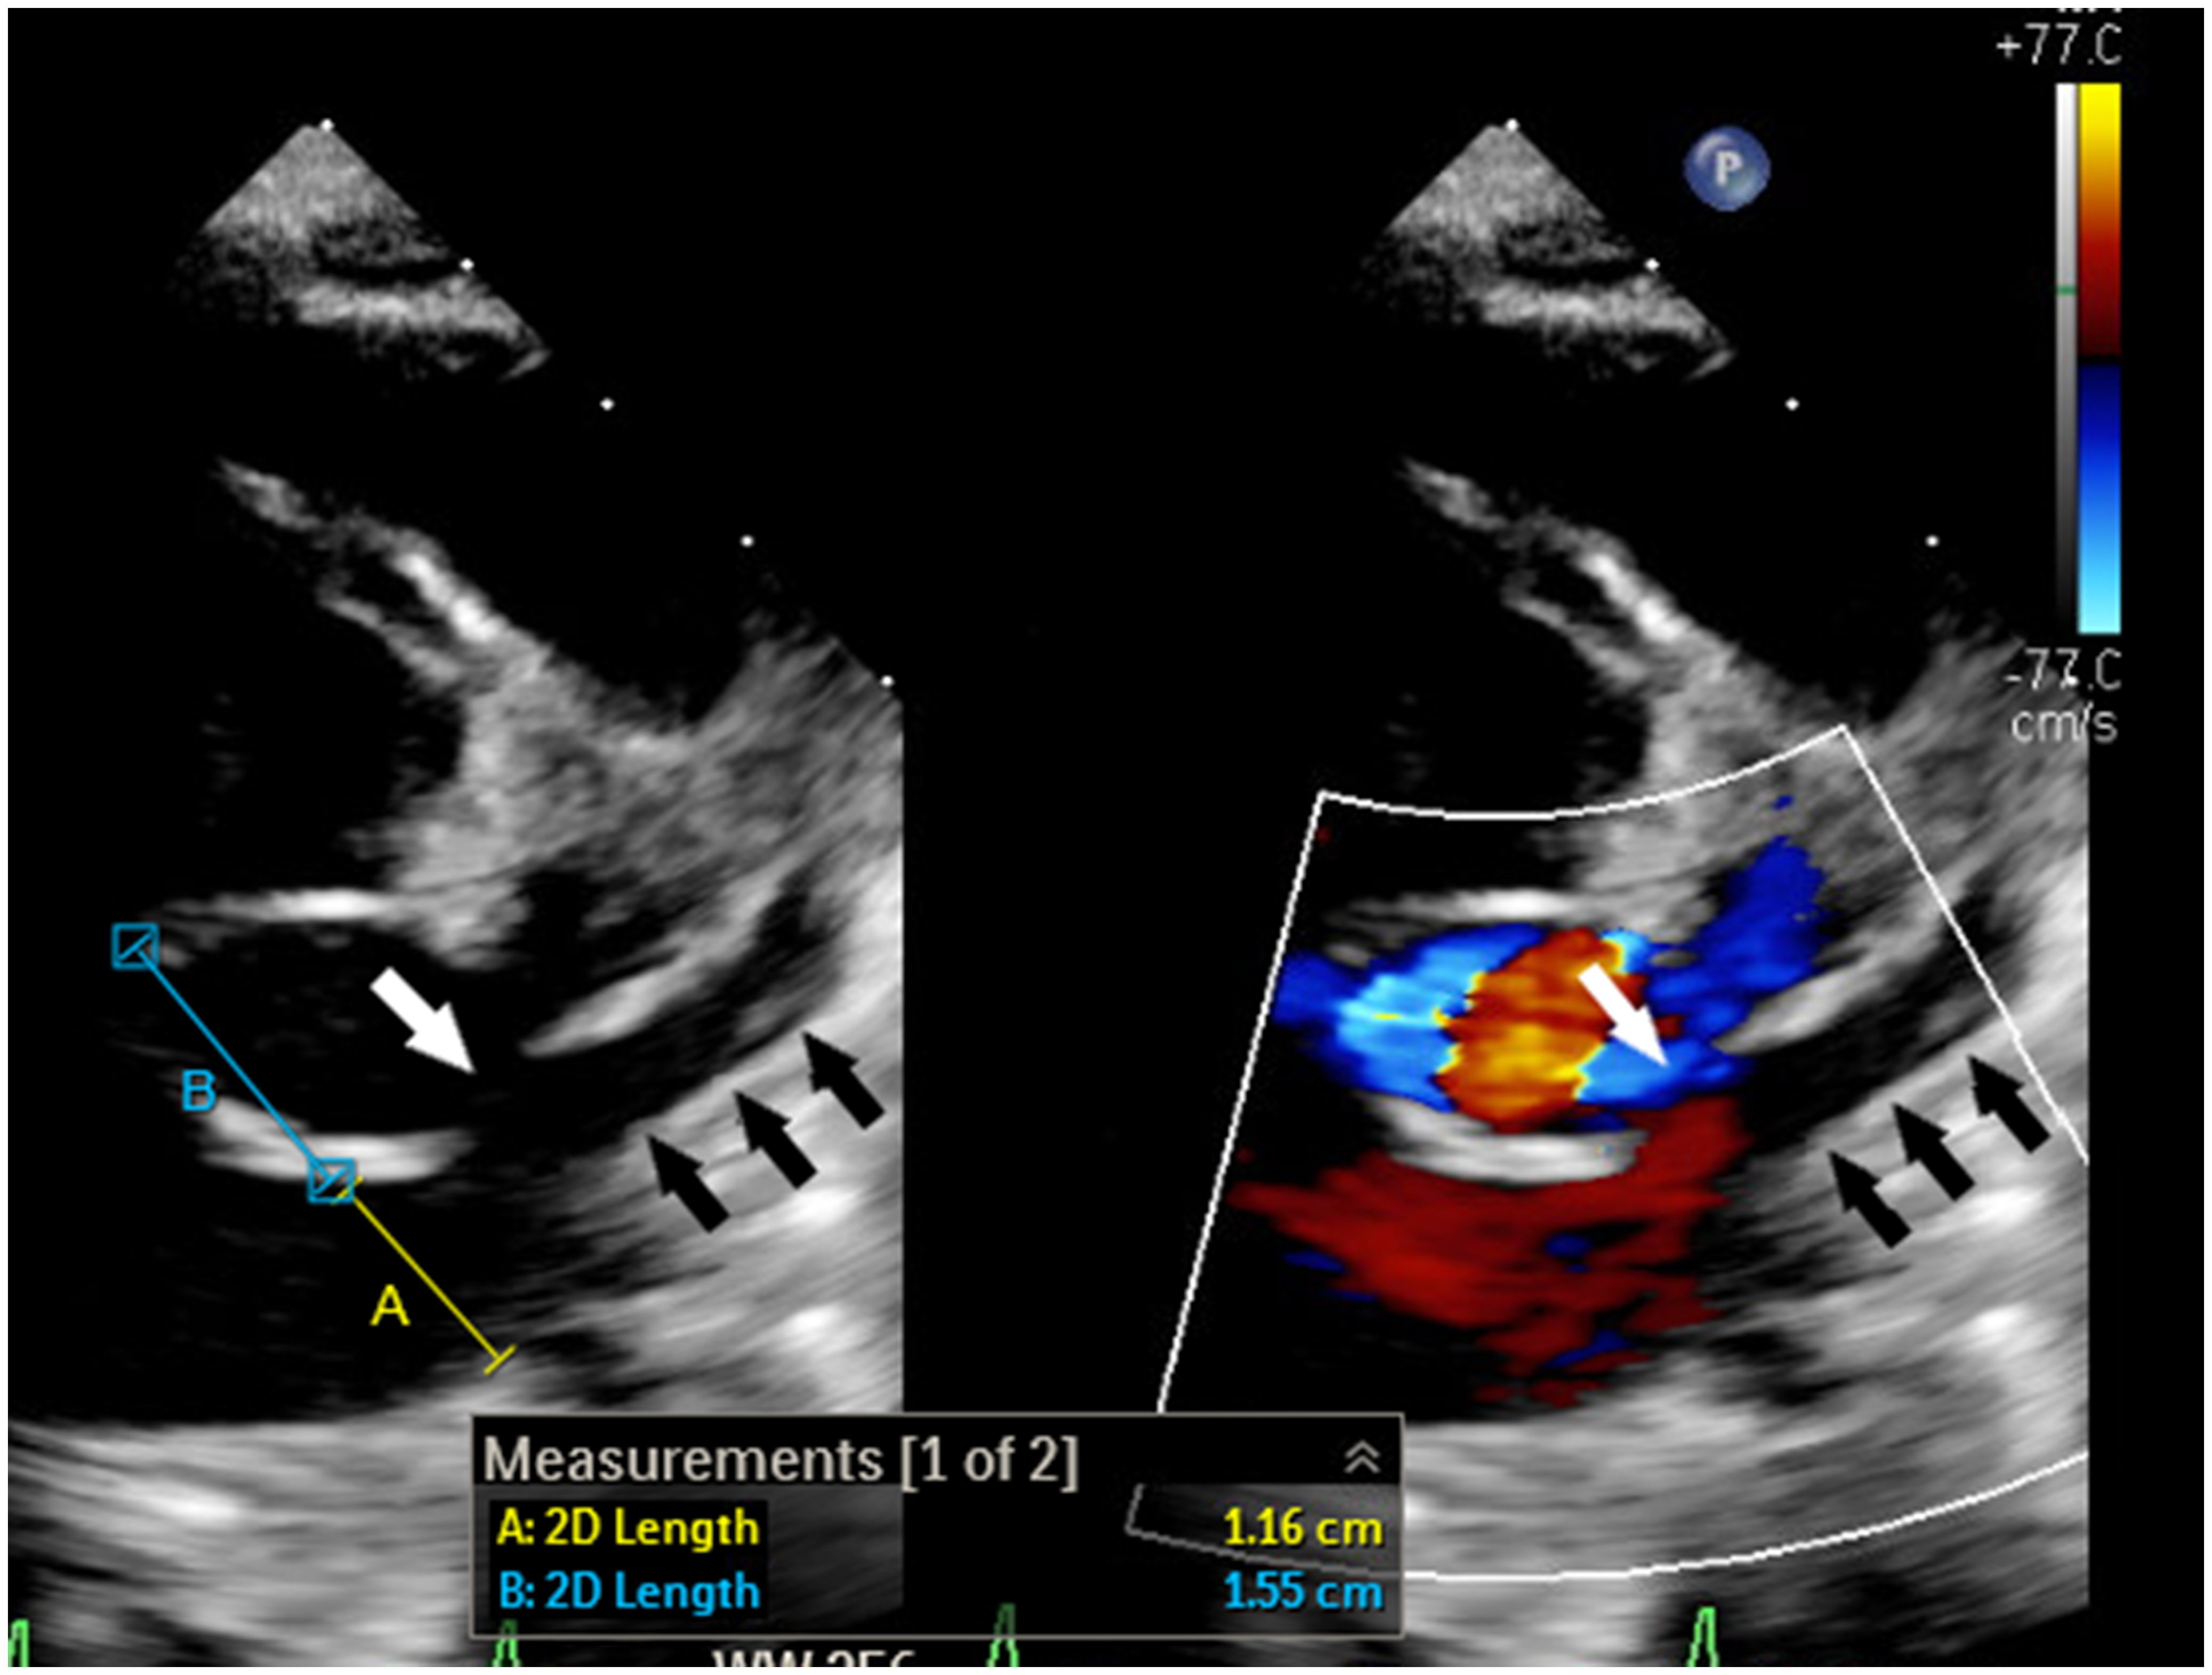

Figure 1. 2-Dimensional echocardiogram with and without colour shows dilated coronary sinus ostium (A) with short septal length (B) and partially unroofed coronary sinus (black arrows). The unroofed segment is depicted with the white arrow.

Despite the advancement in surgical and transcatheter treatments, the prognosis of extensive primary pulmonary vein disease continues to be poor with an estimated mortality rate of 40–50% at 1 year. Reference Vanderlaan, Rome, Hirsch, Ivy and Caldarone1–Reference Khan, Qureshi and Justino4 When the atrial septum is intact, transcatheter pulmonary vein intervention requires creating an atrial septal defect which is challenging and carries substantial risks, especially in young infants. Reference Srinivas, Singla, Reddy, Nagesh and Nanjappa5 Moreover, the presence of the dilated coronary sinus further complicates the safety of the procedure as the septal length becomes significantly shorter (Fig 1). Reference Muller, Backhoff and Schneider6 In the described case, the coaxial system of the 5-Fr JR 4 guide, 4-Fr Jr 2 catheter, and guidewires allowed us to cross the unroofed coronary sinus into the left atrium and the stenotic common left pulmonary vein, with relative ease. In addition, the 5-Fr guide catheter (with an outer diameter of 1.67 mm) enabled us to deploy the stent without the need to exchange for a long sheath. Due to the antiproliferative effect, drug-eluting stents slow the progression of pulmonary vein disease when compared with bare-metal stents. Reference Khan, Qureshi and Justino4 Although exclusive balloon angioplasty is an attractive treatment option, the likelihood of complete occlusion is higher when compared with stent placement. Reference Buiatti, von Olshausen and Martens7 As our patient has a common left pulmonary vein, occlusion would result in complete loss of the physiologic function of the entire left lung which could lead to persistent pulmonary hypertension. Additionally, the presence of a stent will ease transcatheter recanalization should future occlusion occurs as the stent is easily visualized by fluoroscopy. For the future management of the patient, we are planning to perform serial dilation, and we anticipate the need to intentionally fracture the stent to accommodate for somatic growth if a larger diameter is needed. Reference Khan, Qureshi and Justino4